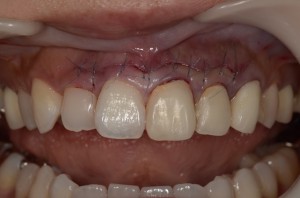

そして、術後3ヶ月でセラミックのかぶせ物を装着したところが、クリニックホームページにありますようにコチラ

8年間の進歩はありますでしょうか?